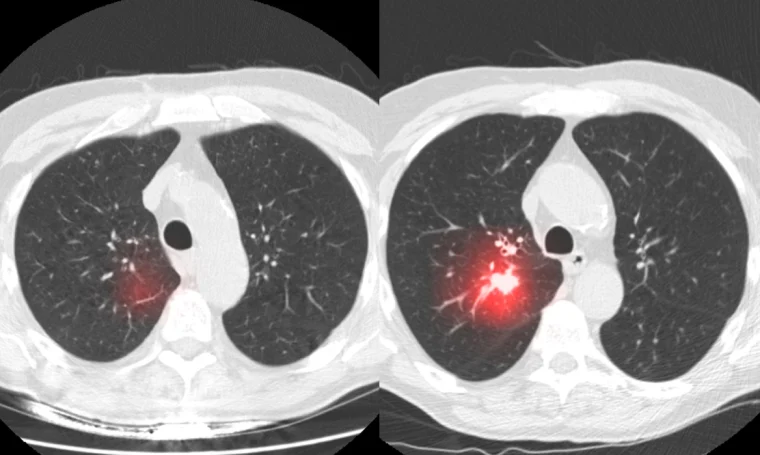

- دستیارهای پزشکی: سیستمهایی که تصاویر پزشکی (مثل CT اسکن) را تحلیل میکنند و به پزشکان در تشخیص بیماریهایی مانند سرطان کمک میکنند. برای مثال، یک سیستم هوش مصنوعی میتواند تومورهای کوچک را که ممکن است از چشم پزشک دور بمانند، شناسایی کند.